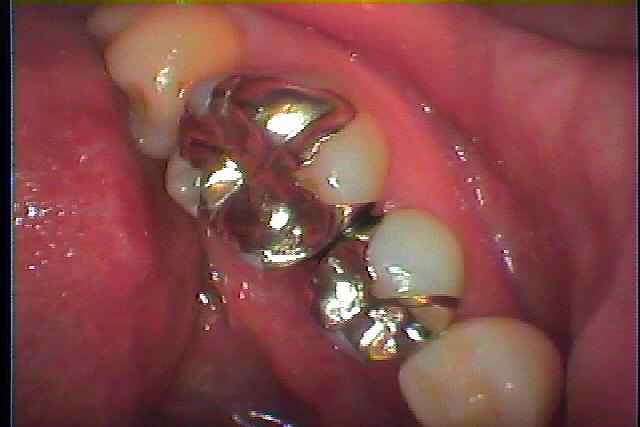

抜歯から3か月、インプラント最終補綴へ 抜歯してから半年後に埋入すれば、10か月 いろいろあると1年かかる場合があります